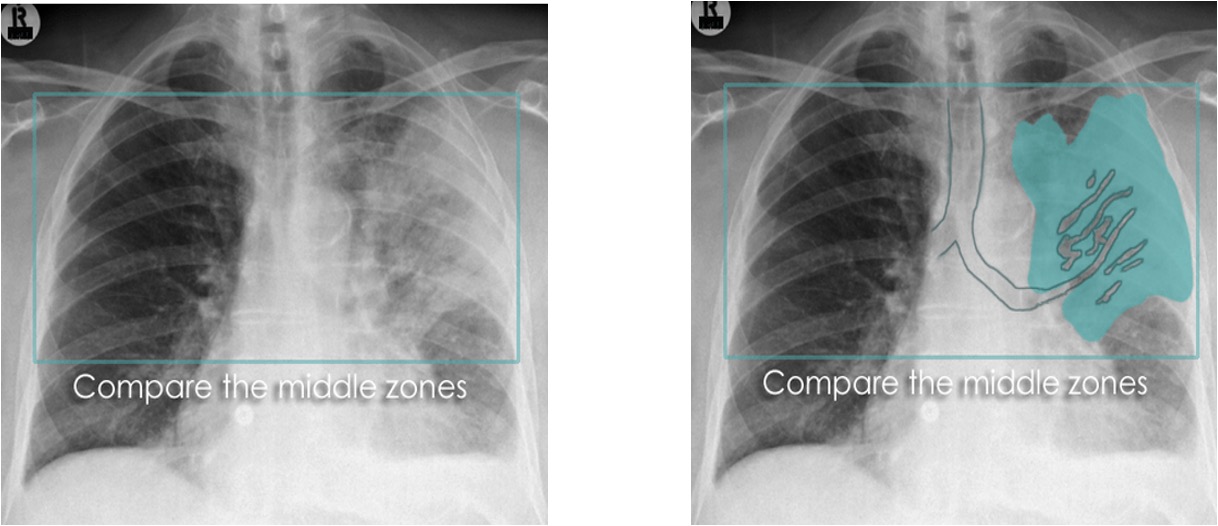

Pleural Effusion

____ is defined as the accumulation of fluid in the pleural space.

____ is seen in the costophrenic angle only (seen on Lat. views), unless it is a high level ___ (Lat. and PA views).